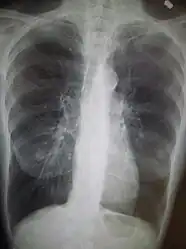

A chest X-ray and complete blood count may be useful to exclude other conditions at the time of diagnosis.[82] Characteristic signs on X-ray are hyperinflated lungs, a flattened diaphragm, increased retrosternal airspace, and bullae, while it can help exclude other lung diseases, such as pneumonia, pulmonary edema, or a pneumothorax.[83] A high-resolution CT scan of the chest may show the distribution of emphysema throughout the lungs and can also be useful to exclude other lung diseases.[25] Unless surgery is planned, however, this rarely affects management.[25] A saber-sheath trachea deformity may also be present.[84] An analysis of arterial blood is used to determine the need for oxygen; this is recommended in those with an FEV1 less than 35% predicted, those with a peripheral oxygen saturation less than 92%, and those with symptoms of congestive heart failure.[24] In areas of the world where alpha-1 antitrypsin deficiency is common, people with COPD (particularly those below the age of 45 and with emphysema affecting the lower parts of the lungs) should be considered for testing.[24]